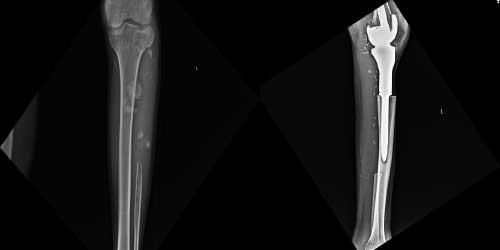

Her ameliyatın olduğu gibi kemik ve yumuşak doku tümör ameliyatlarının da riskleri vardır. Bu riskleri genel ve yapılan ameliyata özgü olmak üzere kabaca iki başlık halinde gruplandırabiliriz. Öncelikle anestezi ile ilgili risklerin anestezi uzmanı tarafından (...)

Ameliyat sonrası takip ve kontrol hastanın ameliyat masasında uyanması ile başlar. Özellikle damar ve veya siniri ilgilendiren ameliyatlarda hasta ameliyat masasından alınmadan ekstremitenin dolaşımı ve ilgili sinirin fonksiyonu kontrol edilir.